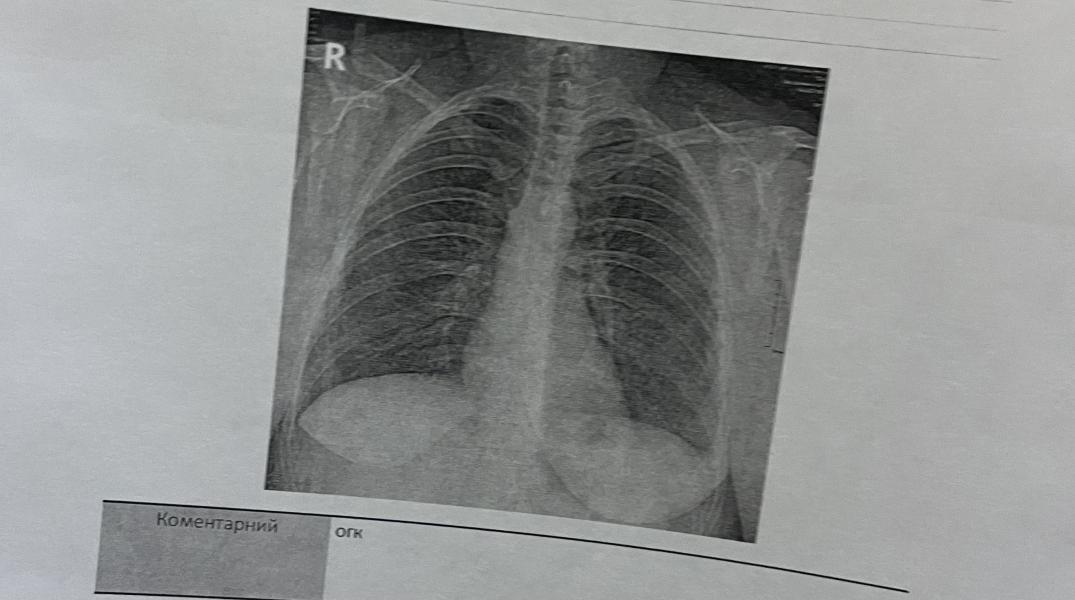

Три разных врача и 2 разных мнения. Может кто умеет читать рентгены. Видно пневмонию?

@annamirag0610, корень легкого особенно справа структурный , нижняя доля правого легкого не видна хорошо. Неявное что-то. Может просто по типу бронхита.

Я бы тоже сказала больше данных за бронхит, возможно. Очагов и инфильтрации действительно не видно на первый взгляд.